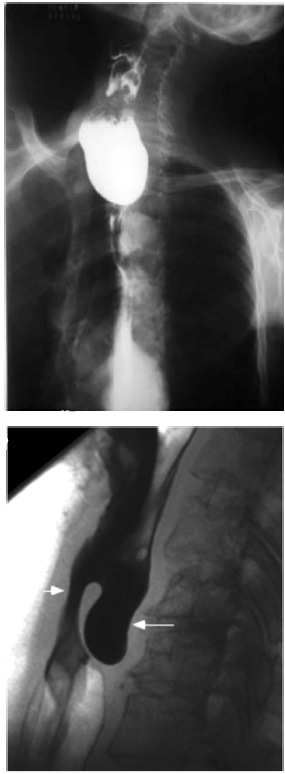

Um paciente de 62 anos de idade, tabagista (1maço/dia) e etilista (5 doses de destilado/dia) há 40 anos, procurou atendimento ambulatorial com queixa de disfagia progressiva (sólidos para líquidos), linfonodomegalia cervical bilateral e perda de 8 kg em seis meses. Foi submetido a estudo contrastado do esôfago, que demonstrou falha de enchimento irregular.

No que se refere ao caso clínico citado, a localização mais comum dessa patologia é

Diante dessas informações, qual é a principal hipótese diagnóstica?